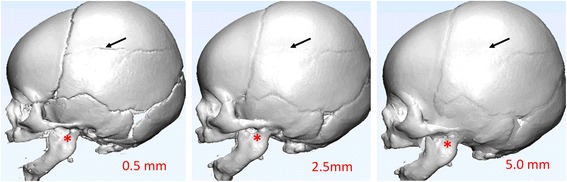

It is essential to check for accuracy of the segmentation and processing as the last step before printing. This can be achieved by overlaying the final STL files on top of the original source images (Fig. 6). Users should inspect the entire image set in all three (axial, coronal and sagittal) planes as errors may be more obvious in one plane than the other. This is especially important if the segmentation process is performed primarily in one plane (e.g. axial). Final approval from the radiologist should be obtained before sending the model to the printer.

Fig. 6.

A renal mass model (a) with segmented results overlaid on original images in axial (b), sagittal (c) and coronal (d) planes. Different colors indicate different segmented objects